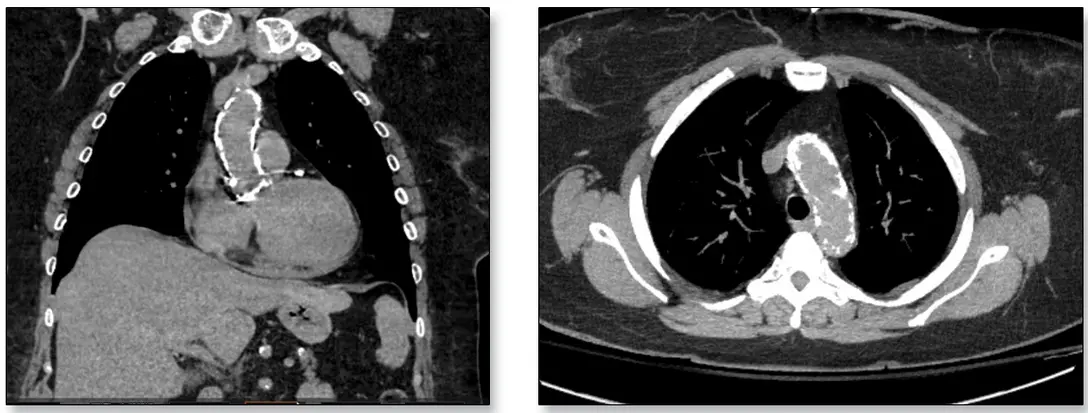

- “porcelain” aorta

- risk of cross-clamping the calcific aorta